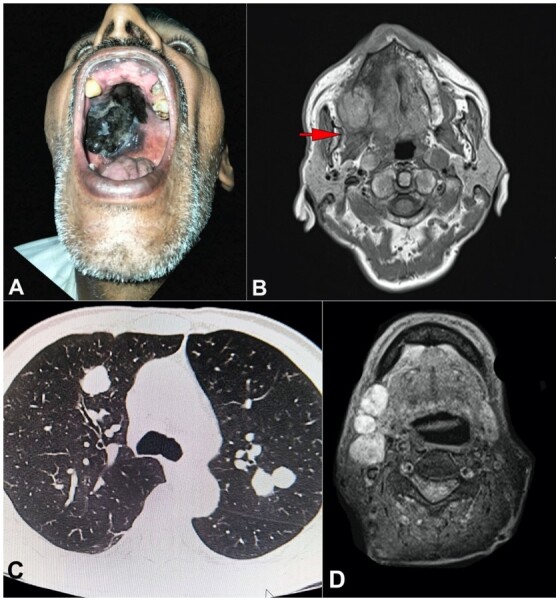

发生在硬腭的黑色素瘤极为罕见,只占所有黑色素瘤病例的一小部分。由于缺乏特异性临床表现,常常导致诊断延迟,给治疗计划带来挑战。我们讨论了现有文献,以阐明与硬腭黑色素瘤相关的流行病学、风险因素和分子途径。此外,我们还讨论了由皮肤科医生、耳鼻喉科医生、肿瘤科医生和病理学家共同参与的多学科方法在诊断和治疗这种疾病方面的重要性。一名 62 岁的男性患者因硬腭粘膜色素性病变就诊,起初无症状,但病变逐渐增大。活组织检查发现了黑色素瘤,并通过免疫组化染色得到证实。分期检查显示为转移性疾病。计划进行手术,然后进行辅助治疗,但他失去了随访机会。源于硬腭粘膜的黑色素瘤极为罕见,给诊断和治疗带来了挑战。早期发现、准确诊断和及时的多学科治疗对取得最佳疗效至关重要。本病例强调了对不常见的粘膜黑色素瘤患者进行全面评估和采取针对性治疗策略的重要性。

Melanoma arising in the hard palate is an exceedingly rare entity, comprising a minute fraction of all melanoma cases. The absence of specific clinical signs often leads to delayed diagnosis and subsequent challenges in treatment planning. We discussed the existing literature to elucidate the epidemiology, risk factors, and molecular pathways associated with melanoma of the hard palate. Additionally, we discuss the importance of a multidisciplinary approach involving dermatologists, otolaryngologists, oncologists, and pathologists in diagnosing and managing this condition. A 62-year-old male patient presented with a pigmented lesion on the hard palate mucosa, which was initially asymptomatic but gradually increased in size. Biopsy revealed melanoma, confirmed through immunohistochemical staining. Staging investigations indicated a metastatic disease. Surgery followed by adjuvant therapy was planned; however, he was lost for the follow-up. Melanoma originating from the hard palate mucosa is exceedingly rare, posing diagnostic and therapeutic challenges. Early detection, accurate diagnosis, and prompt multidisciplinary management are crucial for optimal outcomes. This case underscores the importance of comprehensive evaluation and tailored treatment strategies in patients with uncommon mucosal melanomas.